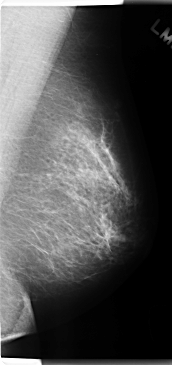

C_0201_1.LEFT_MLO

LEFT_MLO LINES 4744 PIXELS_PER_LINE 2232 BITS_PER_PIXEL 12 RESOLUTION 50 NON_OVERLAY